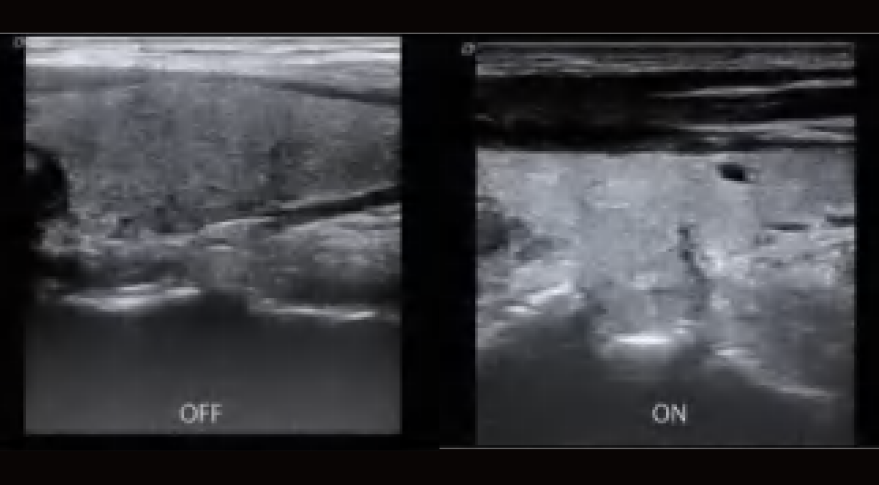

El DW-L50 Exp, impulsado por la avanzada plataforma de ultrasonido ST-U, ofrece imágenes ultra claras en todo momento. Con una movilidad y adaptabilidad sobresalientes, funciona de manera fiable en diversos entornos clínicos complejos. Su introducción permite que más instituciones médicas accedan a tecnología de ultrasonido rentable y de alto rendimiento.